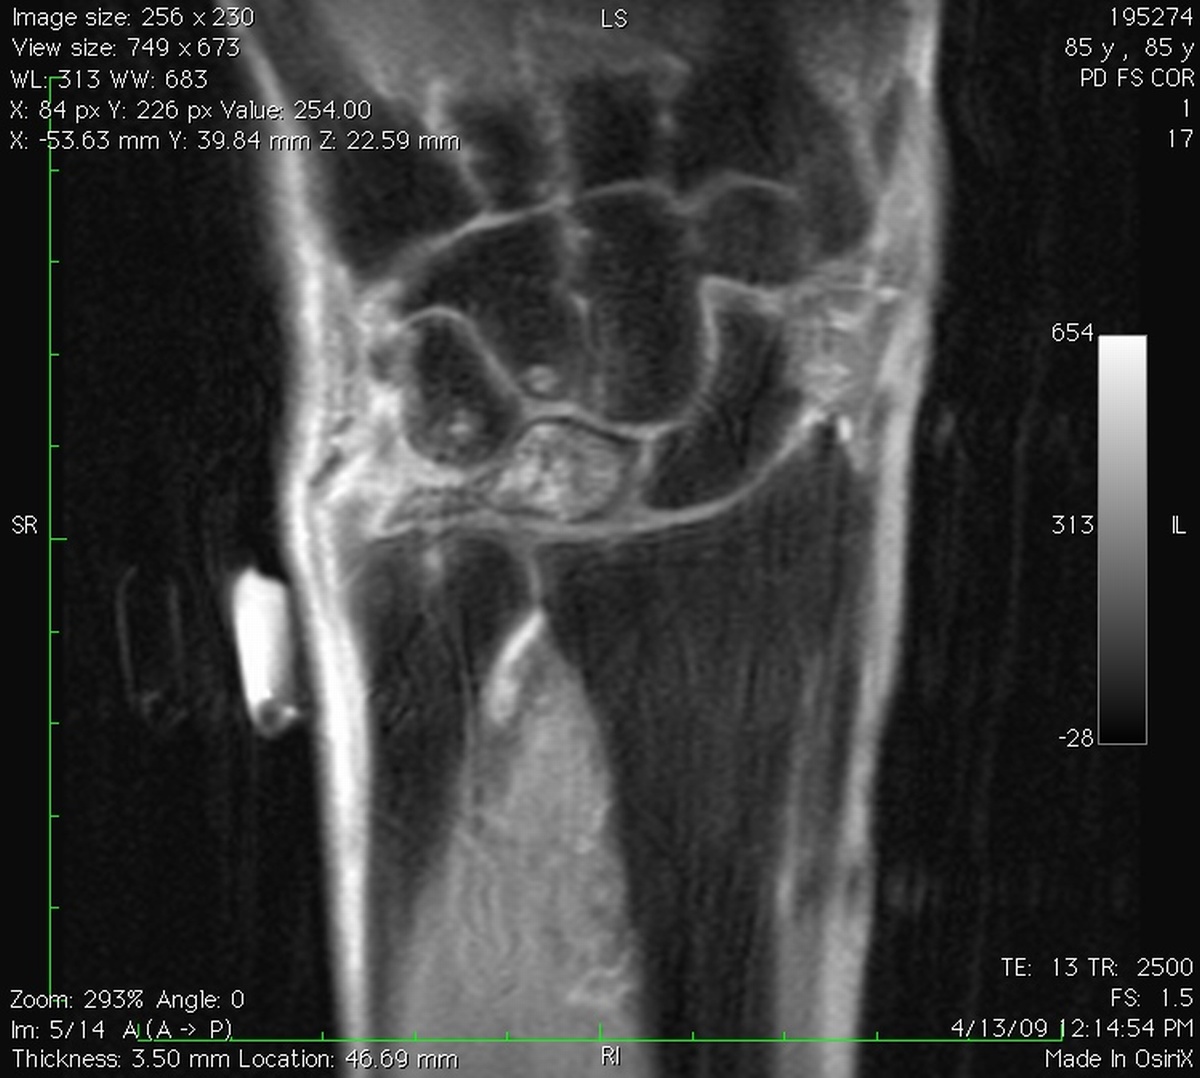

Clinical Example: Lunate Cyst

This imaging series was obtained for evaluation of a one month history of painful pronosupination in an active 85 year old man whose daily exercises include pushups.

lunate cyst